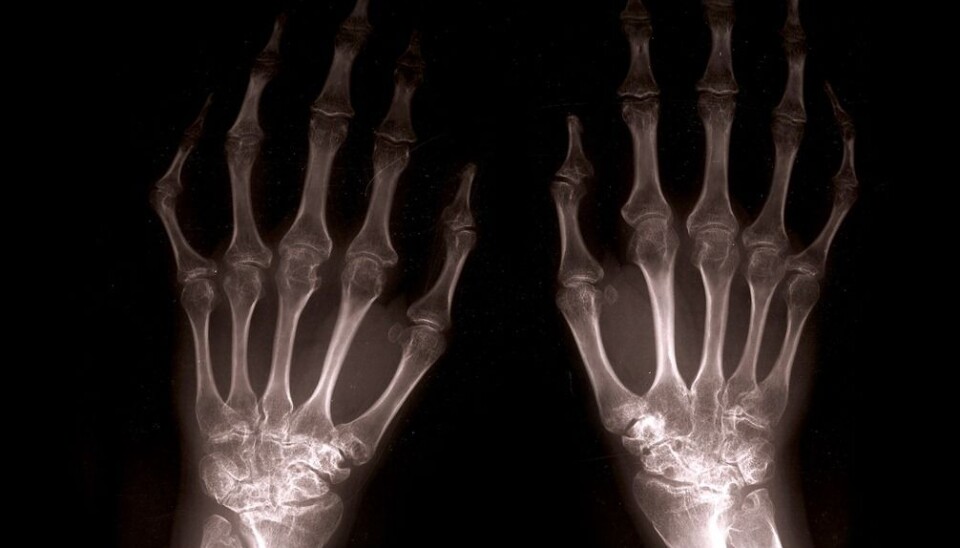

Patients recently diagnosed with multiple sclerosis have low bone density and thus an increased risk of developing osteoporosis.

Low bone density often occurs at an early stage of multiple sclerosis (MS). This is unfortunate because low bone density can result in osteoporosis.

Surprisingly, MS patients had low bone density even at the start of the disease.